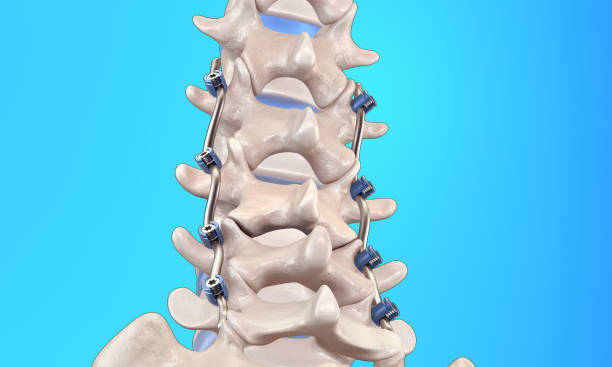

척추관협착증은 척추 주변의 근육과 인대가 퇴행하여 척추관 내 황색 인대가 비정상적으로 부풀어 오르면서 발생하는 퇴행성 척추질환 중 하나입니다. 이 질환은 가까운 거리도 통증으로 인해 걷기가 어려워지는 특징을 가지고 있으며, 새벽에 다리에 통증을 느끼는 경우가 많습니다.

척추관협착증은 다른 척추 질환에 비해 퇴계 정도가 매우 심한 질환으로, 퇴행이 심할수록 근육과 인대가 더욱 뭉쳐지고 더 많은 압력을 가하게 됩니다. 이 때문에 근육과 인대를 풀어주는 것이 중요하며, 이를 위한 가장 적합한 운동이 걷기입니다.